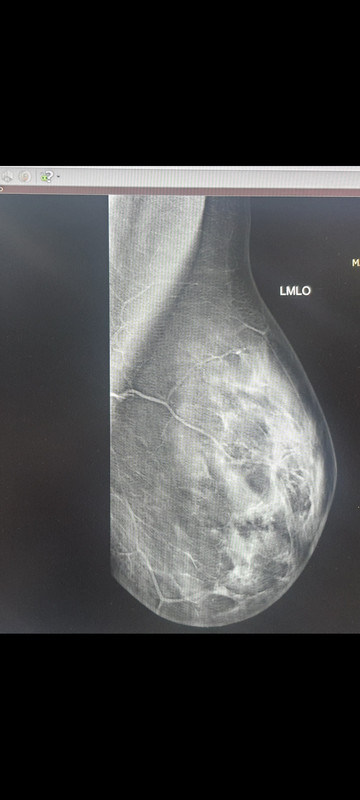

Lo so che oggi è il compleanno del Dott e forse non vorrebbe essere scocciato, ma io ci provo lo stesso: dottore, per la foto che vi ho fatto vedere, quella specie di puntino che si dirama, se non è distorsione, cosa potrebbe essere ? , perché io in quel punto la vedo "non omogenea" ; lo so che mi ha ripetuto più volte che non e' una distorsione, ma cosa potrebbe essere? Mi (sta proprio nel seno sinistro, dove ho retrazione cutanea). Almeno cerco di prepararmi

Rimetto foto: